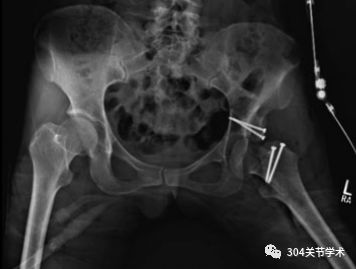

本研究旨在明确关节部分切开联合切开复位内固定术治疗儿童股骨颈骨折是否可降低股骨头骨骺血供破坏的风险。自1989年2月至1994年2月,共纳入13例骨骼发育未成熟的患儿,均接受关节部分切开、清理关节囊内血肿,同时结合切开复位内固定术治疗。其中男3例、女10例;年龄5岁至16岁;骨折原因包括11例交通事故、1例高处坠落以及1例交通事故合并坠落伤。

通过髋关节核磁及其他影像学检查评估术后是否发生股骨头骨骺坏死。患者随访时间为2年至5.5年,平均2年8月。截止末次随访,根据Ratliff 评价标准,12例患者获优良效果,另1例患者获一般效果。无股骨头骨骺坏死、髋内翻、骨折不愈合或骨骺早闭发生。该结果证实了关节切开清理血肿可能会降低儿童股骨颈骨折切开复位内固定术后股骨头骨骺缺血坏死的风险。

典型病例:6岁女,A、B显示III型移位型股骨颈骨折,移位程度占30%-40%;C 伤后48h内,行关节切开血肿清理,同时行切开复位克氏针固定术;D术后41月,骨折愈合无并发症发生。